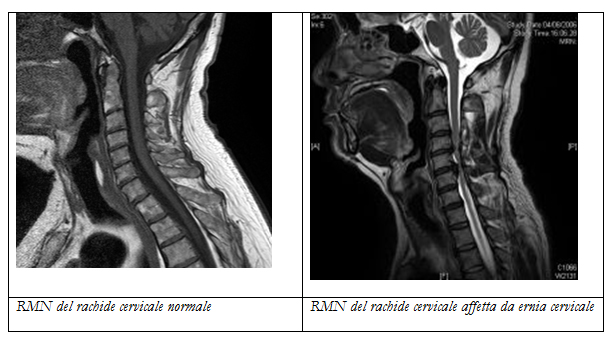

Risonanza magnetica nucleare

La RMN evidenzia le patologie a carico dei dischi intervertebrali e del midollo, inoltre consente lo studio delle radici nervose.